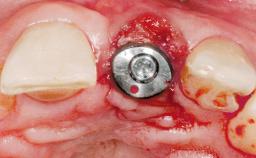

A 36-year-old female patient was referred for the replacement of the upper left central incisor (tooth 21), which had fractured. Although the tooth had been asymptomatic for many years, the crown began to loosen, at which time she presented to her dentist for an assessment. Teeth 21 and 22 had both been endodontically treated many years previously. She was a healthy individual and a non-smoker.

# of Implants | 1 |

Type of Implants | Two-Piece |

Placement Protocol | Early or late implant placement |

Bone Volume | Deficient horizontally, requiring prior grafting |